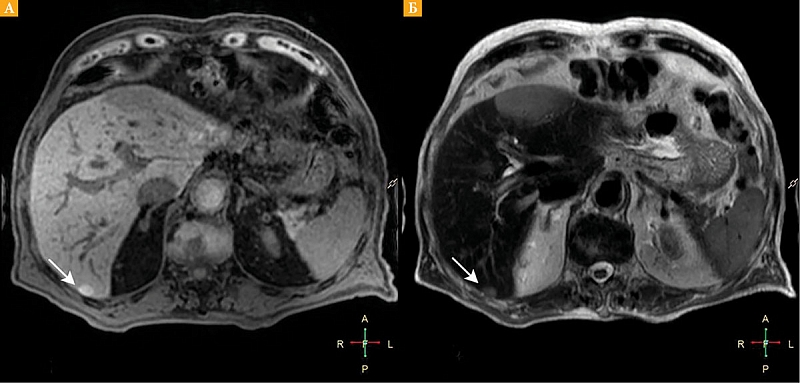

Рис. 4. Форма роста метастазов увеальной меланомы в печень: красная стрелка – инфильтративная форма роста, белая стрелка – узловая форма; DIXON (William Thomas Dixon technique) out of phase (А, Б); Т2-ВИ – коронарная плоскость (В)

Мы предположили у двух пациентов инфильтративный характер роста метастазов в синусоидальном пространстве, а у остальных девяти — узловой в перипортальной области. Предположения сделаны на основе локализации, очертаний и форм образований, в соответствии с гистологической классификацией моделей роста метастазов УМ H.E. Grossniklaus.

Сопоставляя результаты наших исследований с гипотезой H.E. Grossniklaus, мы определили у двух из десяти пациентов инфильтративный характер метастазов, а у остальных восьми – узловой. У одного нашего пациента в одной доле печени наблюдались разные модели роста метастазов (рис. 4). На основании анализа данных МР-исследований в динамике мы предположили, что узловой и инфильтративный характер метастазов – это стадии единого метастатического процесса.